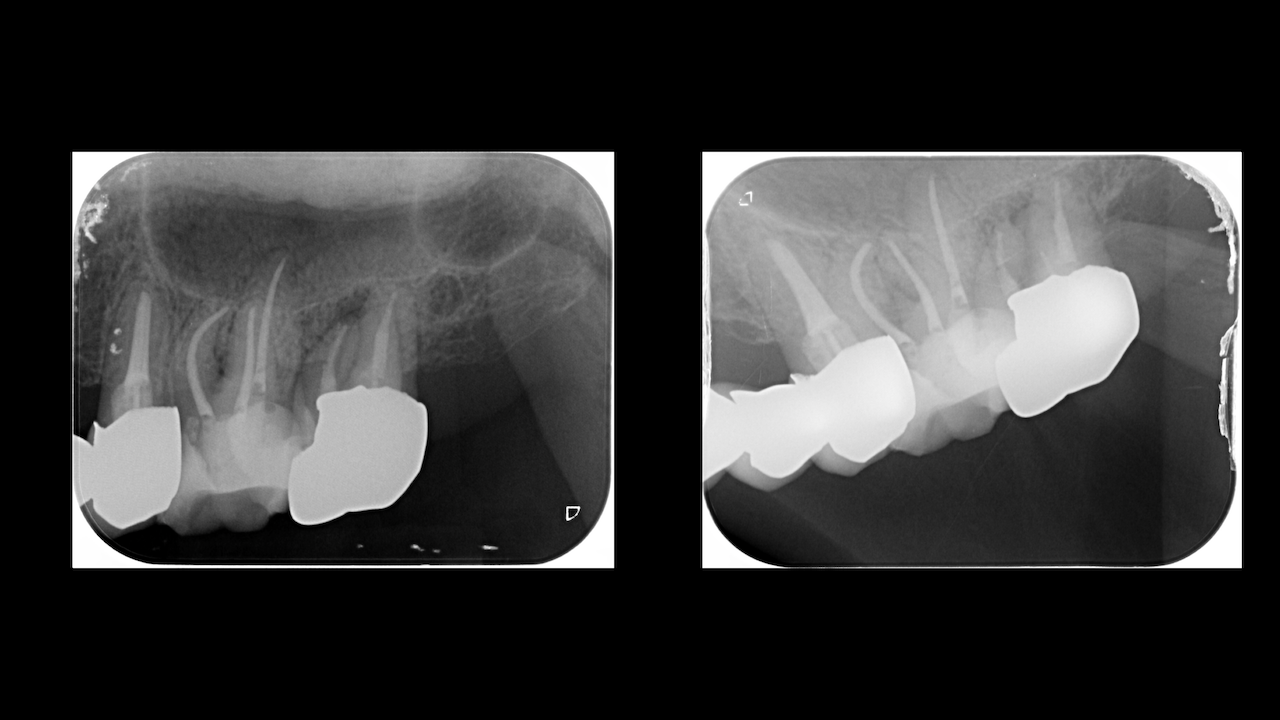

もう1ケースが以下だ。

#7がCold testに無反応である。

故に、#7,8の非外科的根管治療を行うことになった。

が、#8のメタルコアは外しにくいだろう。

CBCTでは2本とも口蓋側の皮質骨が消失している。

という絶望的な状況である。

ここから4ヶ月が経過すると…

臨床症状も皮質骨も大きく治癒している。

1年後の予後が気になるところであるが、すごくよくマネージメントできているだろう。